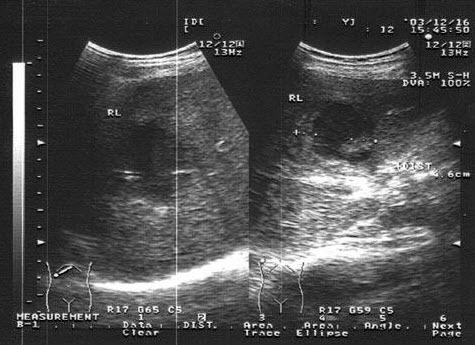

E.彩色血流显像的滤波

35、单项选择题

男,48岁,上腹胀痛,纳差,血吸虫病多年。结合超声声像图,诊断为()

A.血吸虫肝纤维化

B.脂肪肝

C.细菌性肝脓疡

D.肝豆状核变性